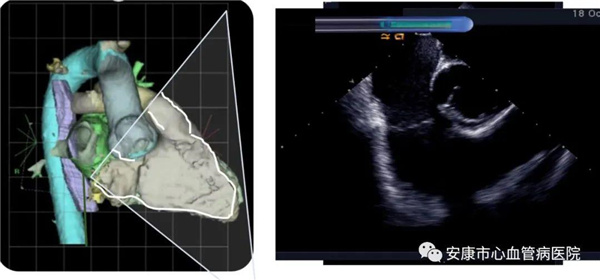

心律失常團(tuán)隊在11月6日為患者在ICE引導(dǎo)下行房撲射頻消融術(shù)。穿刺左鎖骨下靜脈,導(dǎo)絲走行證實(shí)了合并永存左上腔靜脈。穿刺右股靜脈,分別送入心腔內(nèi)超聲導(dǎo)管和消融電極,超聲下建立右心室、右心房、左心室、左心房、二尖瓣和三尖瓣及三尖瓣峽部模型。ICE就像術(shù)者多了一雙天眼,可以對心臟內(nèi)部結(jié)構(gòu)一目了然,360度無死角觀察心臟結(jié)構(gòu),可以做到“所視即所及”。建模后,消融三尖部峽部,房撲很快終止,轉(zhuǎn)為竇性心律,手術(shù)獲得成功!手術(shù)用時僅70分鐘,術(shù)后病情穩(wěn)定,安全返回病房。

心腔內(nèi)超聲(Intracardiac Echocaiography ICE)是將微型的換能器安裝在心導(dǎo)管的尖端,再經(jīng)外周血管(動脈或靜脈)送至心腔,換能器發(fā)射聲波,然后將接受到的回波經(jīng)計算機(jī)處理后形成超聲圖像。由于換能器放置在心腔內(nèi),不受空氣等因素的干擾,因此比經(jīng)食道超聲檢查圖像更加清晰,可以辨別心內(nèi)的細(xì)微結(jié)構(gòu),臨床上主要用于指導(dǎo)心律失常的射頻消融治療。

ICE不僅能檢查左心耳結(jié)構(gòu)、指導(dǎo)房間隔穿刺,而且能精確構(gòu)建左房及肺靜脈解剖結(jié)構(gòu),量化前庭部位與肺靜脈口部的距離,精準(zhǔn)的消融一些復(fù)雜心律失常病例;并且能精確構(gòu)建食道,量化食道與后壁的距離,降低食道損傷幾率;術(shù)中動態(tài)監(jiān)測積液變化,實(shí)時監(jiān)測并發(fā)癥,早發(fā)現(xiàn)早處理。因此心腔內(nèi)超聲真可謂是房顫射頻消融手術(shù)安全保障的一只“天眼”。此外這只“天眼”現(xiàn)在還應(yīng)用于心臟瓣膜手術(shù)、起搏器植入等心臟介入手術(shù)。